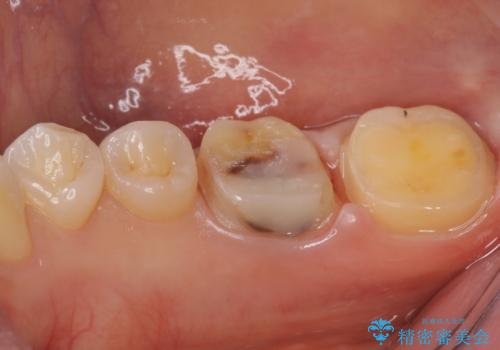

変色した樹脂の詰め物 セラミックでのやり替え

奥歯が樹脂の詰め物で継ぎ接ぎになっていることが確認されたため、今後の虫歯リスクを減らすために適合の良いフルジルコニアクラウンを入れていきます。

樹脂で継ぎ接ぎになった歯はそうでない歯と比べて虫歯になるリスクが高いです。

樹脂をすべて取り、虫歯も取り切った後に適合の良いクラウンを装着することで今後の虫歯リスクを減らすことができます。